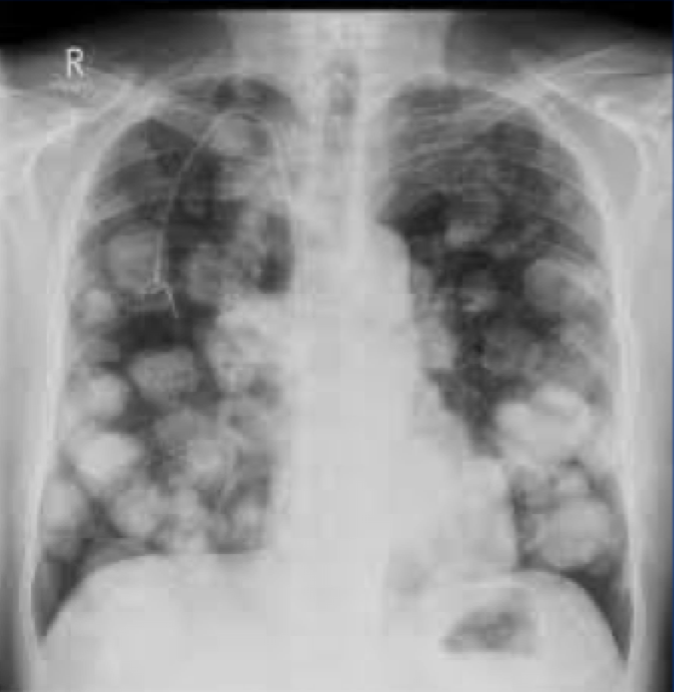

?

A

Cannonball lesions = metastatic lung cancer

- multiple spherical densities with sharp margins

-MC: lower lung zones

MC = ASYMPTOMATIC

May present with:

-Cough, hemoptysis

-Dyspnea and hypoxemia (advanced)

-Symptoms are more often referable to the site of the PRIMARY tumor

17

Q

CT: metastatic lung cancer**

CT is more sensitve …………….